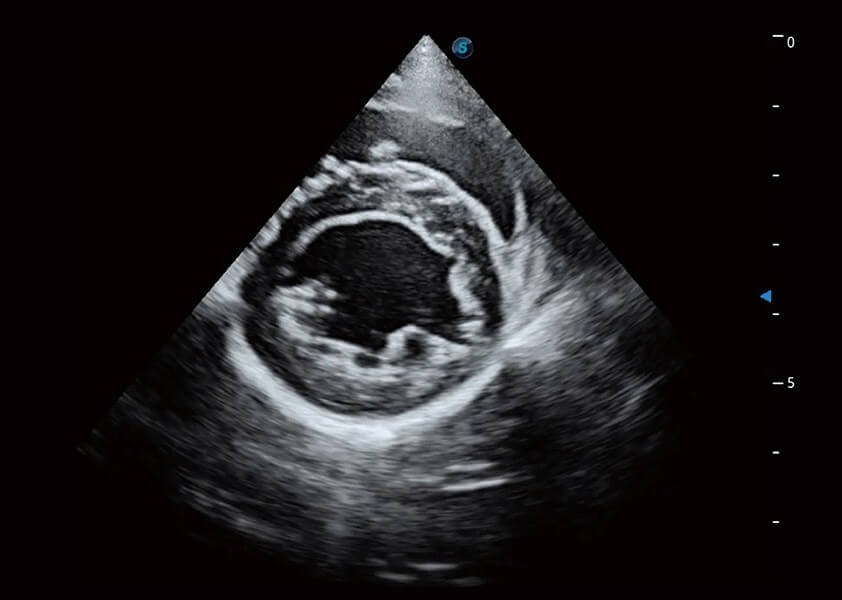

ProPet 60 作为一款高端台式动物超声设备,为动物医生的日常诊断提供了一系列贴合动物临床需求、解决临床实际问题的高级成像功能。凭借全系列高清探头,满足医生对腹部、心脏、生殖、浅表、肌骨等成像的所有需求,切实帮助您提升检查效率,提高诊断信心。

动物是人类最亲密的朋友和最值得信赖的伙伴。美狮贵宾会官网也一直致力于探索动物专用的超声影像解决方案。 全新推出的ProPet系列,是美狮贵宾会官网在动物超声影像智能化、专业化、精准化的一次跨越式革新。动物不能用言语来表述自己的不适,通过超声影像,ProPet系列搭建了动物医生与不同物种沟通的“桥梁”,为动物医生注入了“治愈之力”。